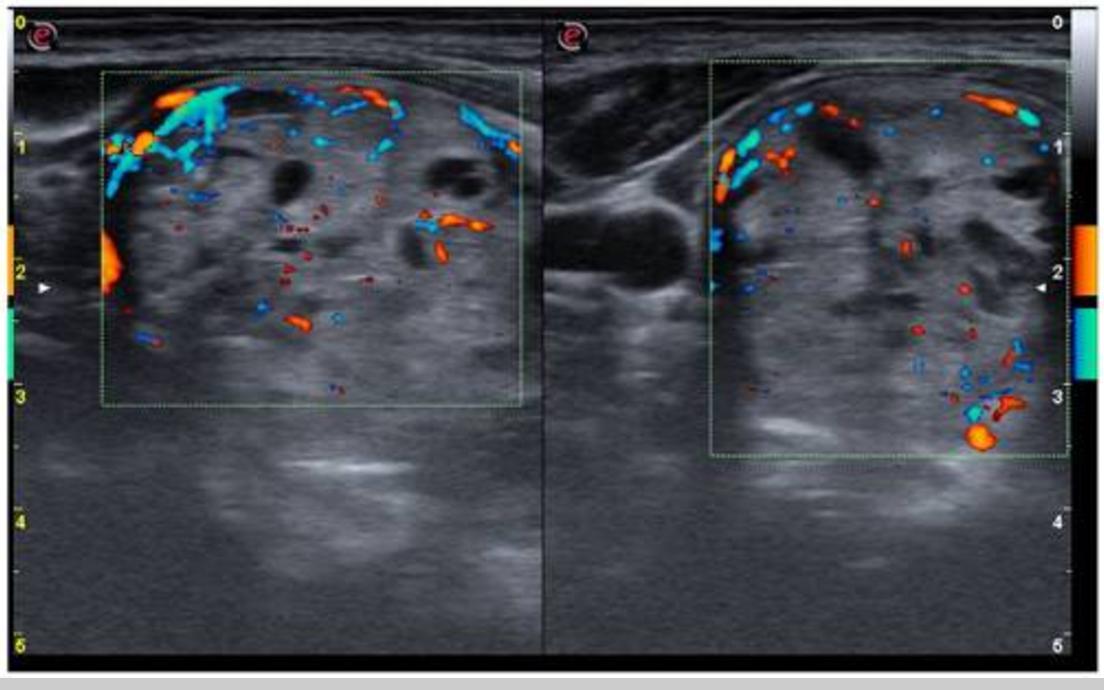

颈部超声检查见甲状腺实质低回声,甲状腺体积增加(26.8 ml,正常上限<16 ml)。右叶被海绵状结节完全取代,血管增加(图1),ACR-TIRADS将其归类为良性(2级)。左叶血管增多,见一个6/5/7mm的部分囊性结节(图2),ACR-TIRADS也将其归类为良性(2级)。

图2 左甲状腺叶血管增加,见一个实性结节(横切面)